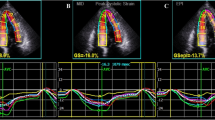

Longitudinal LV strain at rest was quantified in the three apical views using the two-dimensional speckle-tracking echocardiographic method [5, 16] GLS was presented in magnitude throughout the manuscript. LS was assessed in the three apical views using Echopac® software version BT 11.3 (General Electric Medical System®, Horten, Norway), enabling transmural (common LS) and both endocardial and epicardial strain analyses. Adequate tracking could be verified in real time and corrected numerically by adjusting the region of interest or manually by correcting the contour to ensure optimal tracking of LV hypertrophic myocardium. We also calculated the mean LS in hypertrophied segments for each patient and that of the LV basal segments.

LV LS strain analysis was feasible and obtained for 179/217 (82%) patients. We obtained relatively good intra- and inter-observer reproducibility for global LV LS (variability of 3.4 and 4.2%, respectively), regional transmural LS (variability of 8.2–12.2%, respectively), regional endocardial (variability of 7.8–12.8%, respectively) LS, and epicardial LS analyses (variability of 8.9–13.0%, respectively).

The mean global LS (GLS) was 15.7 ± 4.0%; mean transmural GLS in the hypertrophic area was 14.2 ± 4.1%, and transmural LS in the basal segments was 13.6 ± 3.7%.

During a median follow-up of 2.8 ± 1.5 years, ten events occurred (four SCDs and six appropriate ICD shocks) for the 179 patients. In the Cox univariate analyses (Table 4), only maximal wall thickness, and mean LV LS in hypertrophic area were significantly predictive of SCD and appropriate ICD shock (p < 0.05), particularly transmural LS (HR = 0.83 [95% CI 0.72–0.95], p = 0.01). As multicolinearity between maximal wall thickness and LS in hypertrophic area was detected by a VIF test > 3.0, we did not performed any Cox multivariate analysis. Kaplan–Meier survival curves of (transmural) LS in hypertrophic area predicting SCD or appropriate ICD shock are presented in Fig. 2 (p for log-rank = 0.014). Figure 3 displays an example of a patient.